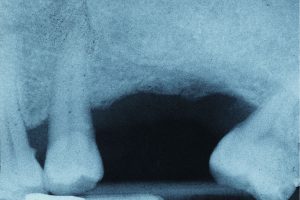

X-ray of missing toothWe will ensure that the extraction process is as comfortable as possible. Once profound anesthesia is achieved, the tooth will be removed. Instructions will be given to ensure proper post-operative care and a speedy recovery.

Removing a tooth could lead to the shifting of neighbouring teeth, resulting in problems with chewing and joint function. Of course, loss of a front tooth is also an aesthetic concern. We will also be happy to discuss different ways a missing tooth can be replaced.